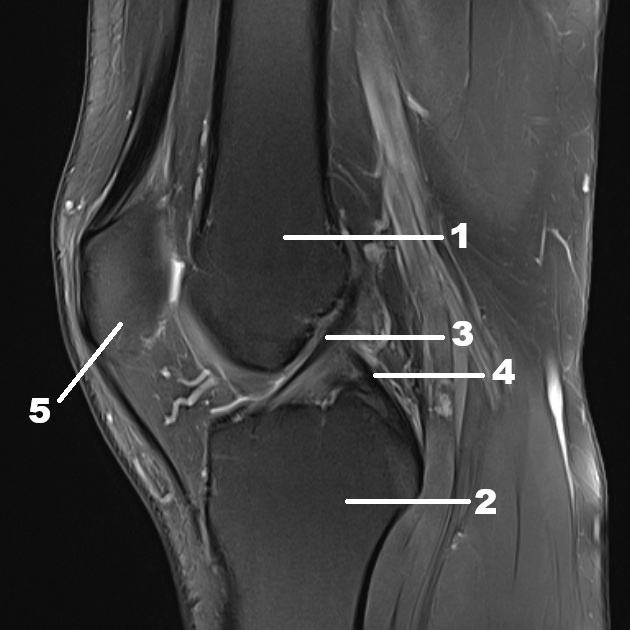

Рисунок 1. МРТ-снимок из личной практики. Нормальная анатомия сустава (26 лет). Бедренная кость (1), большеберцовая кость (2), передняя крестообразная связка (3), задняя крестообразная связка (4), надколенник (5).